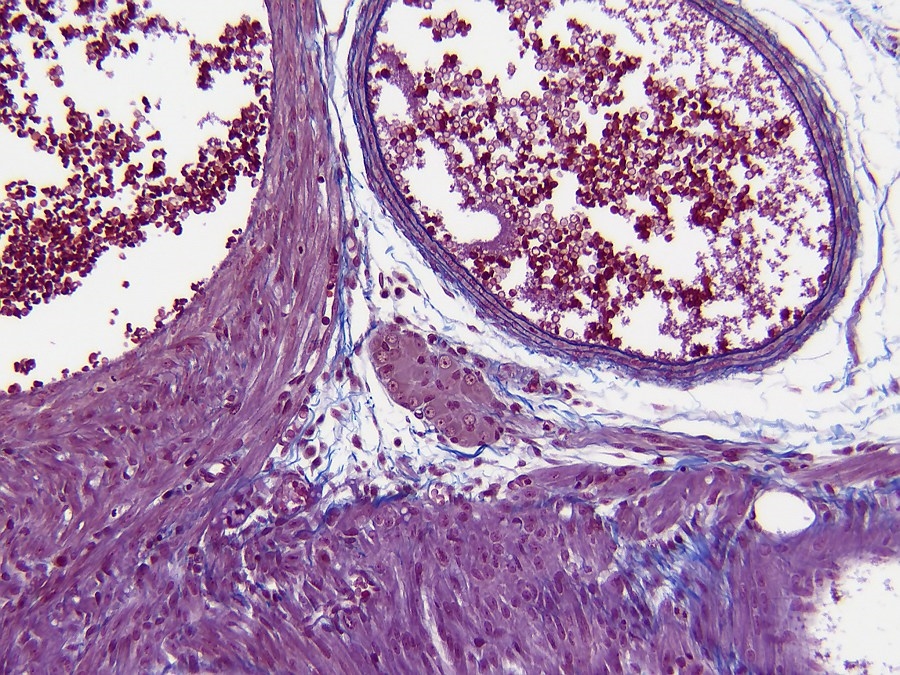

Detaillierter sieht es so aus. Objektiv Plan Fluotar 16x

Objektiv Planapo 40x

Sieht also aus als ob es keine Purkinje Zellen sind, eher ein Normales Ganglion.